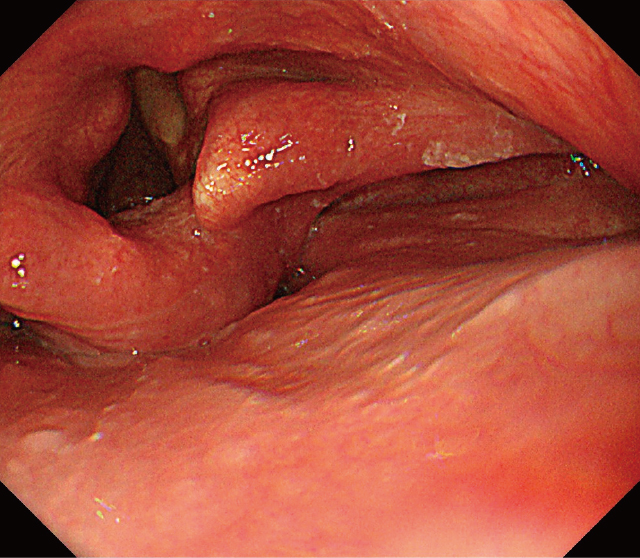

治療経過:画像検査所見より咽頭脂肪腫と診断した.窒息の可能性の回避のため切除が必要と判断し,耳鼻咽喉科の協力の下,ESDを施行した.彎曲型喉頭鏡にて喉頭展開したところ,腫瘍の基部は輪状後部と右梨状陥凹に認め,食道入口部まで十分に観察可能であった(Figure 6).ヒアルロン酸入り局注液で膨隆を得た後,1.5mmのDual knife(オリンパス社製)を用いて病変肛門側である食道入口部の9時方向から切開を開始し,次いで6時方向(輪状後部側),3時方向(右梨状陥凹側),12時方向(披裂側)の順に切開をつなげ全周切開とした.上皮下剝離時,腫瘍の披裂~梨状陥凹側は脂肪が多く血管が目立ったが,通常のESDと同様に一括切除可能であった(Figure 7).術後経過は良好で翌日より食事を開始した.痛みはアセトアミノフェンの内服でコントロール可能で術後4日で退院となった.術後2週間の外来時には痛み,嗄声共になく術後2カ月の内視鏡ではESD潰瘍は治癒し瘢痕化していた(Figure 8).また,患者本人の嚥下時違和感も消失していた.

ESD後2カ月の内視鏡所見.ESD潰瘍は治癒し瘢痕化していた.